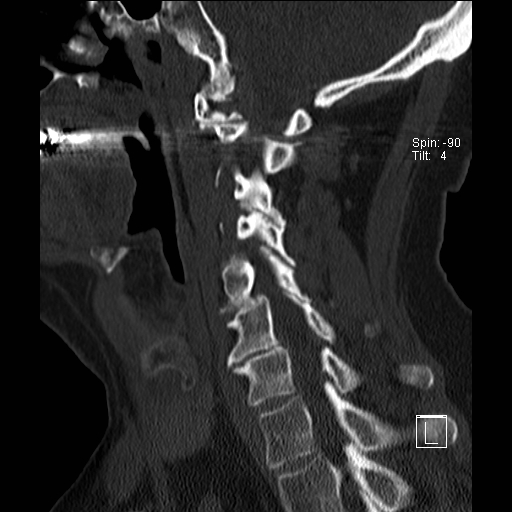

Lồng nền sọ

Lồng nền sọ, còn gọi là sụt lún sọ não hay ấn nền sọ, xảy ra ở 5-10% bệnh nhân viêm khớp dạng thấp cột sống cổ.

Trong lồng nền sọ, mỏm răng sa vào lỗ chẩm làm thu hẹp không gian dành cho tủy sống.

Biểu hiện lâm sàng đa dạng, từ đau đầu mạn tính, hạn chế vận động cổ đến suy giảm thần kinh cấp tính (chèn ép tủy sống và thân não, có thể dẫn đến liệt hoặc thậm chí tử vong nếu cổ bị di chuyển ở một số tư thế nhất định).

Hình ảnh

Cuộn xem các lát cắt CT.

Có hình ảnh di chuyển lên trên của mỏm răng vào lỗ chẩm.